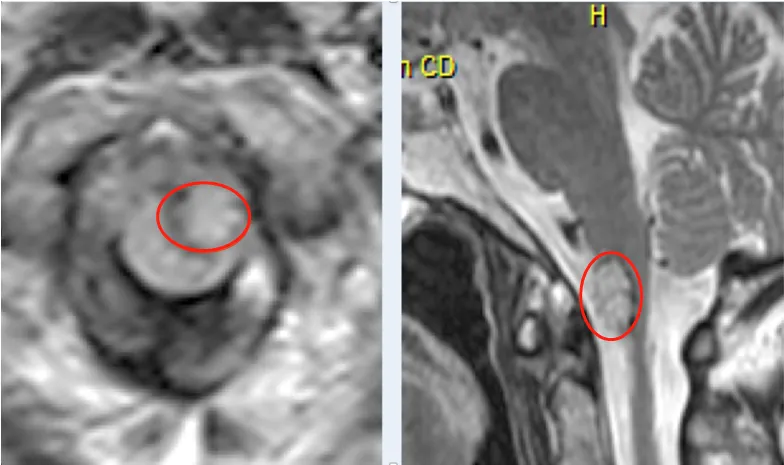

术前MR:高位颈髓-脑干延髓脑桥海绵状血管瘤

脑干-颈髓病变

脑干-颈髓病变可导致患者颈部以下的躯干和四肢瘫痪,甚至不能自主呼吸,终生使用呼吸机,更可直接导致呼吸心跳停止。而且该部位空间极为狭小,手术操作难度极大,病变与颈髓、神经、血管等紧密粘连,稍有不慎都可能出现瘫痪,这可谓是神经外科领域难度极高风险极大的手术之一。